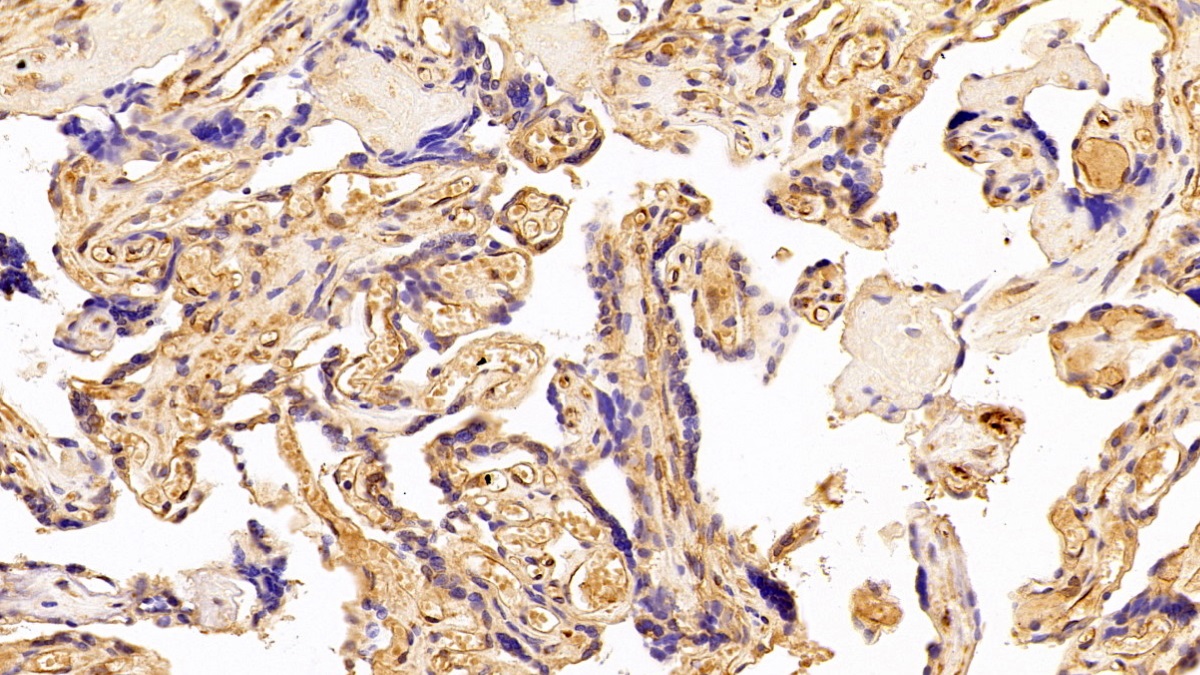

Использование высококачественных первичных антител является неотъемлемым условием получения точных и воспроизводимых результатов в современных научных исследованиях. Например, в рамках онкологического исследования удалось достоверно идентифицировать экспрессию белка PD-L1, что сыграло ключевую роль в оценке потенциальной эффективности иммунотерапии. Применение надежных антител обеспечило стабильность сигнала и высокую специфичность детекции, что позволило получить данные, пригодные для публикации в рецензируемых научных изданиях.

Способы применения первичных антител

Первичные антитела используют в разных методах: от вестерн-блоттинга до иммунофлюоресценции и проточной цитометрии. Всё решает подготовка: нужно грамотно выбрать буфер, точно рассчитать, сколько продукта добавить, и не затянуть с инкубацией. Например, в вестерн-блоттинге без правильной блокировки мембраны фон может всё испортить, а в иммунофлюоресценции фиксация клеток решает, будет ли сигнал ярким. Мы не просто продаём реагенты, а помогаем довести эксперимент до результата: подбираем реагенты и даём советы по методам, если есть специфика в протоколах производителя. Нужен особый подход? Оформите спецзаказ по ссылке — мы найдём решение для вашего проекта.